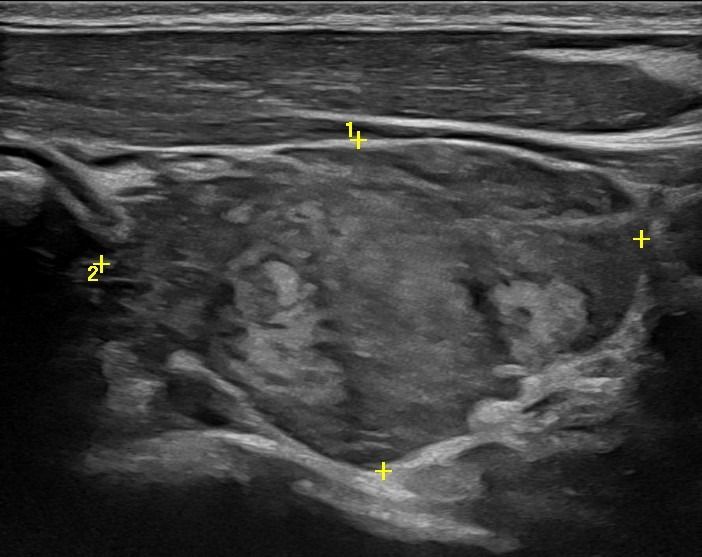

Με την τριπλή μελέτη του Θυρεοειδούς Αδένα, που περιλαμβάνει το B-Μode, το Έγχρωμο Υπερηχογράφημα και την Ελαστογραφία, γίνεται μια ολοκληρωμένη χαρτογράφηση του θυρεοειδούς αδένα. Το περίγραμμα, η αγγείωση και η ελαστικότητα του αδένα, καθώς και η υφή μίας πιθανής βλάβης αξιολογούνται με ακρίβεια και αξιοπιστία.

• Εστιακές αλλοιώσεις (όζοι του θυρεοειδούς αδένα)

• Κακοήθεις βλάβες (καρκίνος θυρεοειδούς)